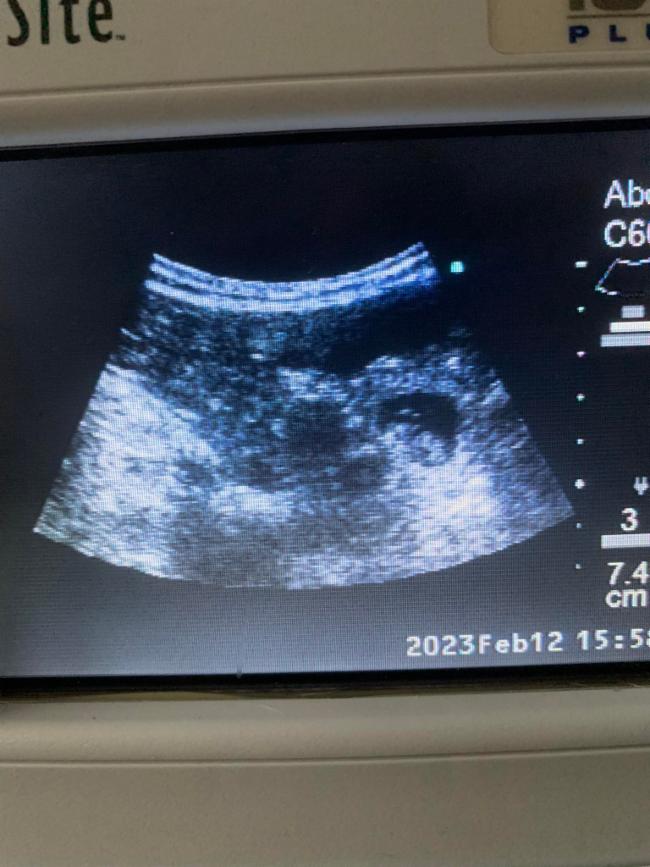

12.02.2023 Juhu, wir sind schwanger!!! <3

13.02.2023 Melodie am 31. Tag der Trächtigkeit!

Ein kleines Bäuchlein ist schon zu sehen, ihr Hunger ist deutlich gestiegen und auch ihr Schlafbedürfnis. Draußen ist sie aber immer noch flott unterwegs. Der Bauchumfang beträgt jetzt 65 cm